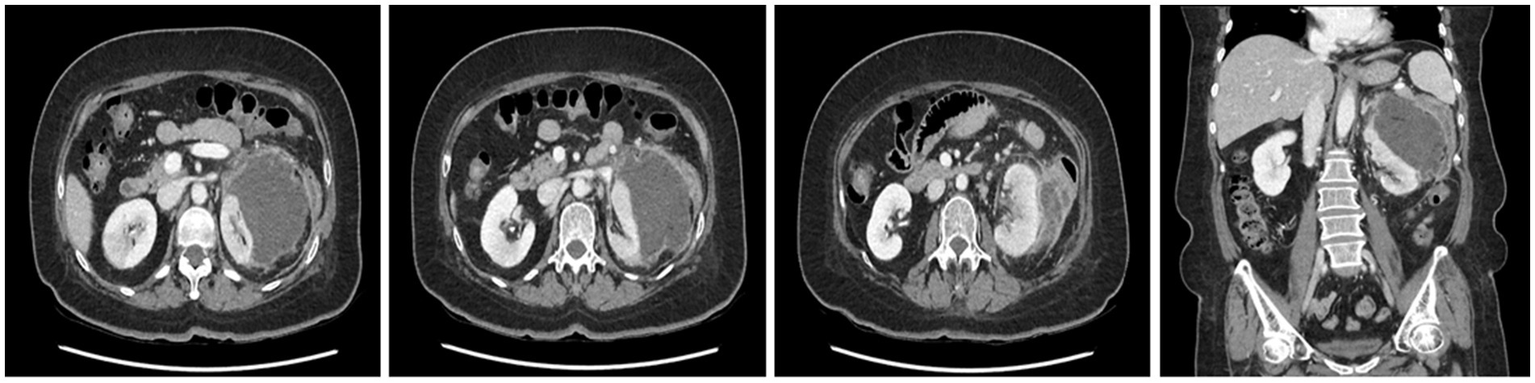

A CT scan performed at the secondary hospital revealed an 8 cm subcapsular hematoma on the left kidney, without evident etiologies causing hemorrhage, and a wedge-shaped density in the right kidney, which was compatible with acute pyelonephritis (APN). No active renal hemorrhage was found on CT (Figure 1). Conservative management, including saline hydration and sugar, blood pressure, and pain control, was carried out, and intravenous ciprofloxacin was administered for APN management after admission. No fever was observed until the 10th day after admission, and vital signs were stable; however, the flank pain persisted. A CECT was performed on the 10th day of hospitalization after the confirmation of restored renal function (serum creatinine: 0.89 mg/dL). The CECT revealed an enlarged fluid collection with peripheral enhancement, suggestive of a perinephric abscess (Figure 2). A percutaneous drainage (PCD) procedure was performed, initially aspirating approximately 100 mL of reddish fluid, and the catheter was left in the hematoma for continuous drainage. Klebsiella pneumoniae grew in the drainage fluid culture and was highly sensitive to ciprofloxacin.

Figure 1

Contrast-enhanced CT showing a non-enhancing subcapsular hematoma measuring 8 cm in length on the left kidney, accompanied by fluid collection in the perinephric space and suspicious wedge-shaped heterogeneous areas of poor enhancement (arrow) representing acute pyelonephritis in the right kidney.